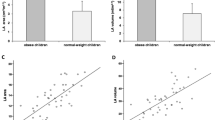

In CMR imaging, subjects with central obesity had significantly increased LVMWT compared to control subjects (12.3±1.2 (8–14) vs. 10.7±1.5 (10–15) mm, p < 0.001) (Figs. 1 and 2; Table 3). The LVMWT exceeded the normal range (6-11 mm) in 20 of 29 subjects with central obesity and four of 18 control subjects (69 vs. 22 %, p=0.002). The maximal wall thickness in the centrally obese subjects was located in the interventricular septum at basal and midventricular levels (Fig. 1B).

Scatterplot of the relationship of left ventricular maximal wall thickness and body mass index (BMI) in centrally obese and control subjects (A). Left ventricular maximal wall thickness (mean and 95 % confidence intervals) in study groups before and after standardization for BMI (B). Stdzd standardized

LVMWT in the centrally obese did not correlate with BMI (r = 0.06, p = 0.757; Figure 2A) or age (r = 0.243, p = 0.100). The difference in LVMWT between the study groups remained significant when adjusted for BMI (p = 0.015), age (p < 0.001), or both (p = 0.012) (Table 3). The BMI-standardized LVMWTs in the study groups are shown in Figure 2B.

EAT area, MAT area, and VAT as well as SAT areas were significantly larger in the central obesity group than in the control group (Figure 3). The difference in IAT area (epicardial plus mediastinal adipose tissue area) between the study groups remained even after adjustment for BMI (p = 0.012), age (p < 0.001), or both (p = 0.021).

EAT area correlated inversely with LVEDV index (r = − 0.403, p = 0.037) and LV SV (r = − 0.425, p = 0.027), and there was a trend for a positive correlation between EAT area and LVMWT (r = 0.368, p = 0.054). MAT area correlated inversely with LV SV (r = − 0.427, p = 0.027) and positively with LVMWT (r = 0.399, p = 0.035). EAT area or MAT area did not correlate with LV mass, LV end-systolic volume, or ejection fraction (data not shown). There was no correlation between EAT area or MAT area and CMR findings in the control group (data not shown).